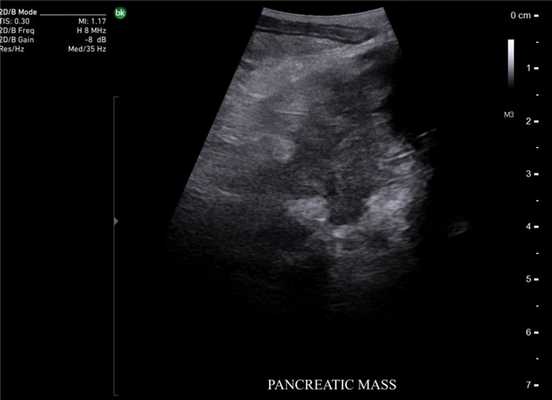

Метастаз печени. Сканирование интраоперационным датчиком 8816

В панкреатологии ИОУЗИ применяют как при доброкачественных процессах, например, при хронических панкреатитах для локализации главного панкреатического протока, выявления вирсунголитиаза, поиска псевдокист в паренхиме поджелудочной железы и стенке двенадцатиперстной кишки, недоступных визуальному осмотру, так и при злокачественном поражении. Наиболее сложным является оценка измененной ткани головки поджелудочной железы с целью дифференциальной диагностики псевдотуморозного панкреатита и рака.

Опухоль поджелудочной железы. Сканирование интраоперационным датчиком 8824